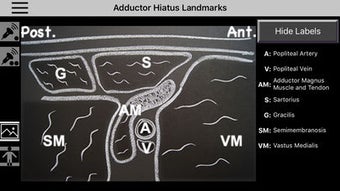

AnSo Anestesia Sonoanatomía es una aplicación para iPhone que proporciona una comprensión integral de la sonoanatomía relevante para el anestesista. Con más de 250 imágenes de ultrasonido y 1500 superposiciones de color de sonoanatomía, esta aplicación es un recurso conveniente diseñado para ayudar a los anestesistas a identificar la sonoanatomía común de manera eficiente en el tiempo dentro del ajetreado quirófano. Creado por anestesistas en ejercicio con interés en la enseñanza de la ecografía y la anestesia regional, AnSo proporciona múltiples ejemplos de la sonoanatomía ya que cada individuo es diferente.